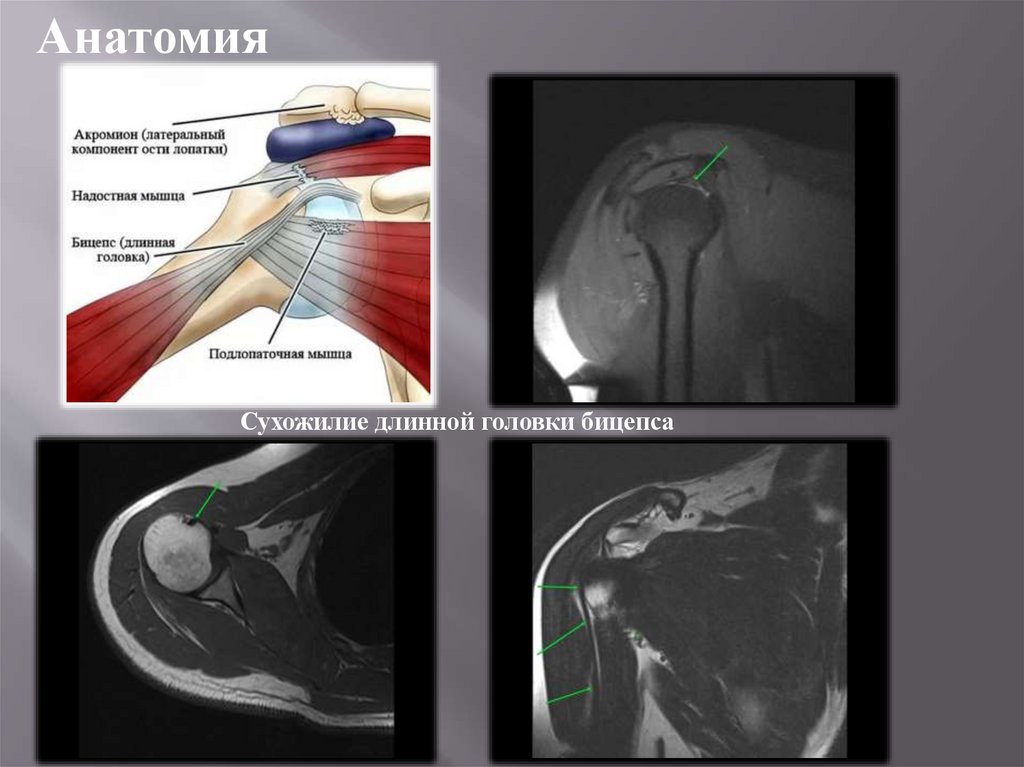

Анатомия

Сухожилие длинной головки бицепса